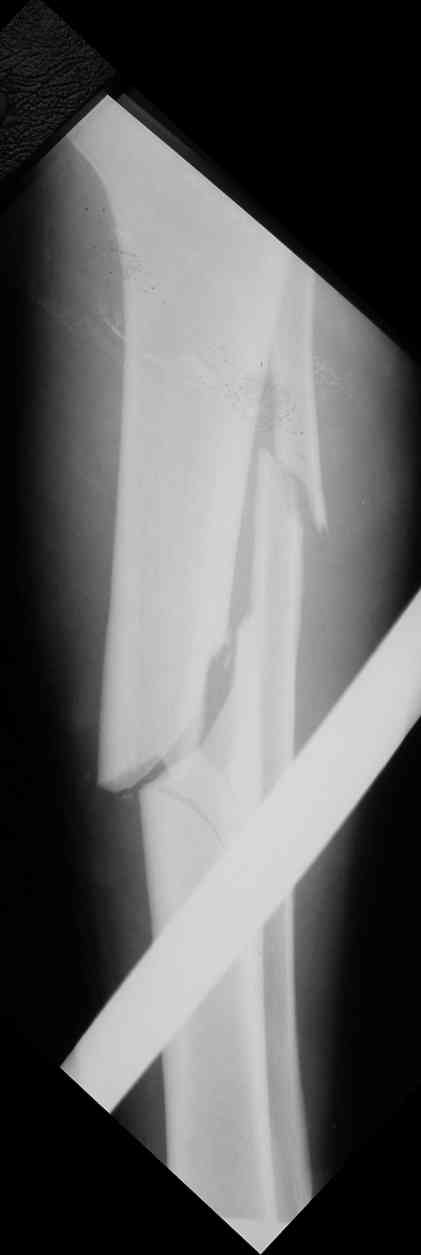

Вчера первый раз синтезировали голень гвоздем Fixion.

Спиральный оскольчатый перелом, ниже середины, у молодого парня. Сделали "классический" вариант гвоздя, который еще без винтов. Получилось все легко. Не торопясь, сделали операцию минут за 20. См. фото.